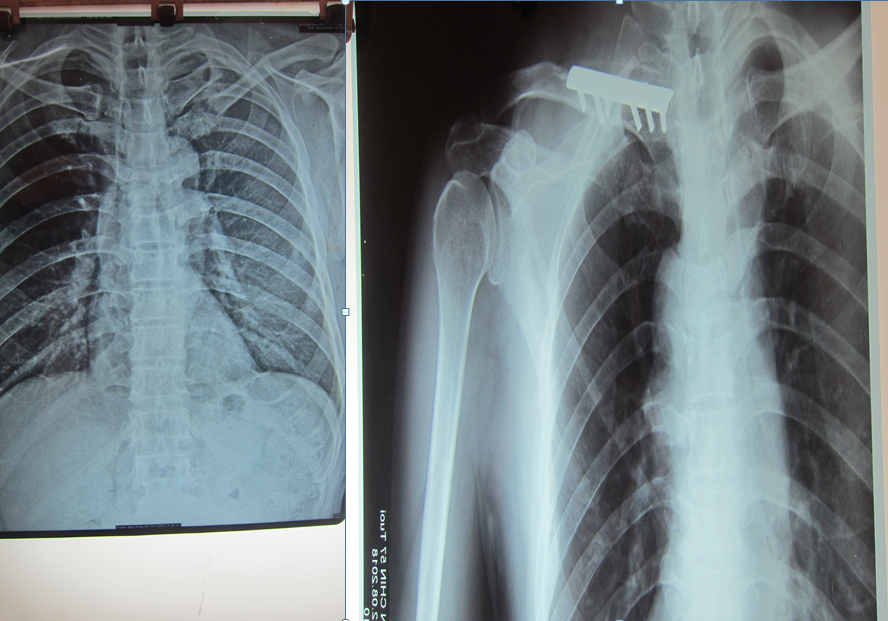

Sáng ngày 21/8/2018, Trung tâm Y tế thành phố Yên Bái tiếp nhận người bệnh Lê Văn Chí, 57 tuổi, thường trú tại tổ 44, phường Hồng Hà, thành phố Yên Bái. Bệnh nhân bị tai nạn ngã xe đập vùng vai xuống nền cứng khoảng gần 1 tháng do không phát hiện bệnh nhân ở nhà thấy tình trạng đau, sưng nề vùng vai trái, hạn chế vận động, chụp Xquang có hình ảnh gãy 1/3 xương đòn trái. Người bệnh được hội chẩn với chẩn đoán gãy kín 1/3 giữa xương đòn trái cal lệnh, được chỉ định phẫu thuật kết hợp xương bằng nẹp vít.

Hình ảnh XQuang trước phẫu thuật